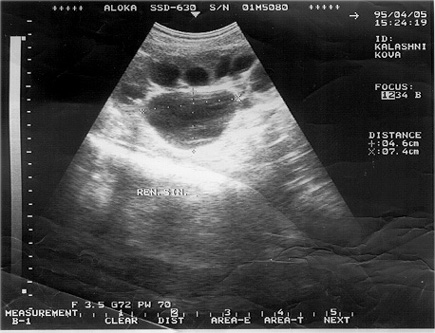

1. Обследование детей начинается с ультразвукового исследования почек и мочевыводящих путей. Исследования выполняются высококвалифицированными специалистами на современной аппаратуре.

В случаях необходимости проведения дифференциальной диагностики между пиелоэктазией и стадией гидронефроза, с целью уточнения характера обструкции – динамическая или органическая, проводится ультразвуковое исследование с диуретической нагрузкой.

Пример:

а) до введения лазикса – лоханка 11 мм, чашечка 6 мм;

б) через 15 мин. после введения лазикса – лоханка 15 мм, чашечка 8 мм;

в) через 30 мин. после введения лазикса – лоханка 24 мм, чашечка 9 мм;

г) через 45 мин. после введения лазикса – лоханка 25 мм, чашечка 9 мм;

д) через 60 мин. после введения лазикса – лоханка 27 мм, чашечка 12мм.